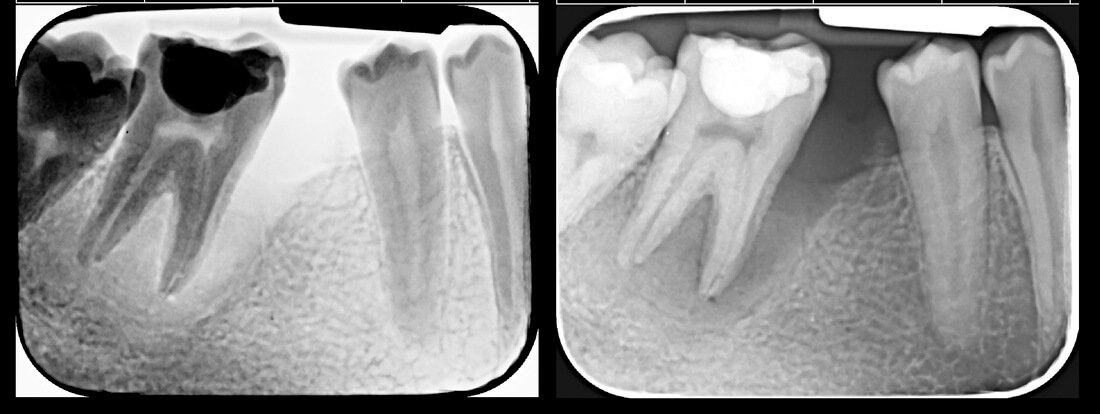

Endodonția este o ramură esențială a stomatologiei, axată pe diagnosticarea, prevenirea și tratamentul afecțiunilor pulpei dentare și a țesuturilor periapicale. Această specialitate joacă un rol crucial în salvarea dinților naturali, evitând extracțiile și menținând sănătatea orală pe termen lung. Prin tehnici avansate și echipamente de ultimă generație, endodonția asigură tratamente precise și eficiente, contribuind la redarea sănătății și funcționalității dinților într-un mod durabil și predictibil.

Tratamentele endodontice permit păstrarea dintelui natural, evitând extracția și menținând funcționalitatea acestuia.

Tratamentele corecte reduc riscul de infecții și complicații viitoare.